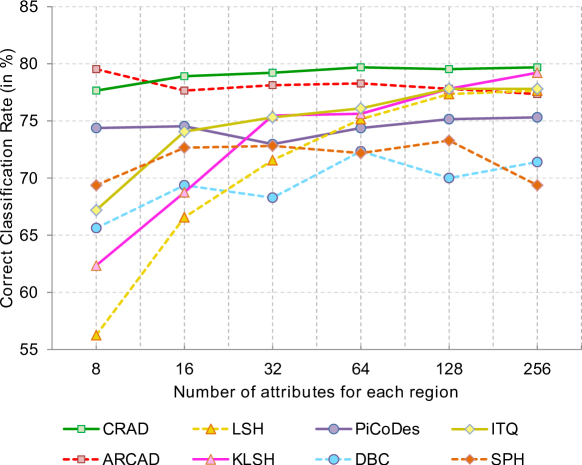

We first contrast the proposed approaches to the recent hashing methods such as: Locality-Sensitive Hashing (LSH) [3], Kernelised LSH (KLSH) [9], Spectral Hashing (SPH) [19] and Iterative Quantization (ITQ) [8]. In addition we also compare the proposed approaches to the recent discriminative attributes learning: PiCoDeS [1] and Discriminative Binary Code (DBC) [16].

All methods were trained and tested using the specimen-level descriptor extracted with the setup previously described. We used the unlifted regional descriptor in conjunction with the histogram intersection kernel for KLSH.

The results are presented in Fig. 3. Both ARCAD and CRAD outperform all other methods even when small numbers of attributes are used. This suggests that the proposed approaches are highly discriminative even with small code length. The learning schemes successfully discover the essential cell attributes which are highly discriminative to form specimen image descriptor. We note that both LSH and KLSH require longer code length to achieve similar performance to the proposed approaches. This is consistent with the finding reported in previous works suggesting that LSH requires longer code length to achieve good performance [9]. In our case having a small code length is advantageous since the experts require less time to name the discovered attributes.

It is noteworthy to mention that the proposed approaches outperform significantly PiCoDeS as well as DBC which were specifically designed to discover the discriminative attributes. Both PiCoDeS and DBC consider attribute value in binary space. Furthermore, the DBC learning scheme operates in the binary space which is intrinsically more complex. In our case, we consider real attribute values (Refer Eqn. 2). In the light of this fact, we argue that presenting attribute value as a the real number is more expressive than a binary value ( i.e. 0 or 1).